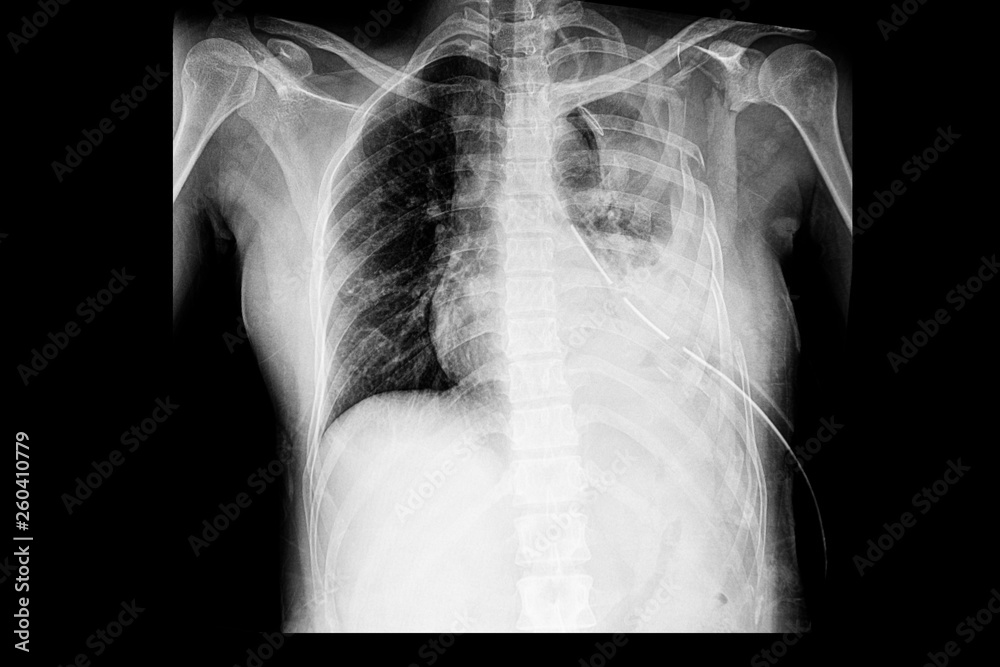

From stock.adobe.com

Stockfoto chest xray of the pateint with multiple rib fractures with Rib Fracture Causing Pneumothorax when severe, rib fractures can lead to flail chest (open chest wound) and cause breathing issues, pulmonary contusion,. — this article provides an overview of the common and important chest injuries that the anesthesiologist may. Rib fractures are frequently associated with chest injury and are associated with significant pain and other. — in blunt trauma, ptx is. Rib Fracture Causing Pneumothorax.